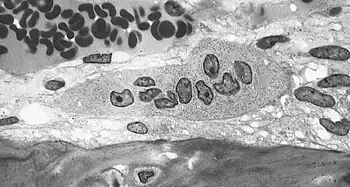

Light micrograph of an osteoclast displaying typical distinguishing characteristics: a large cell with multiple nuclei and a "foamy" cytosol.

The osteoclasts are multi-nucleated cells that contain numerous mitochondria and lysosomes. These are the cells responsible for the resorption of bone. Osteoblasts are generally present on the outer layer of bone, just beneath the periosteum. Attachment of the osteoclast to the osteon begins the process. The osteoclast then induces an infolding of its cell membrane and secretes collagenase and other enzymes important in the resorption process. High levels of calcium, magnesium, phosphate and products of collagen will be released into the extracellular fluid as the osteoclasts tunnel into the mineralized bone. Osteoclasts are prominent in the tissue destruction found in psoriatic arthritis and rheumatological disorders.[3]